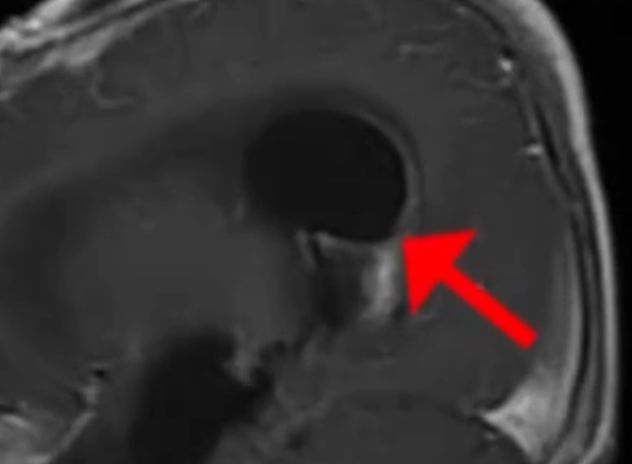

医生随即在这段时间,用核磁给航航检查了脑部。他们在结果中清晰地看到男孩脑部有一个硕大的包块。众人都非常疑惑一岁多的孩子大脑之中怎么会产生这种病变呢?但毋庸置疑的是,正是这包块中的积液让男孩身体不见好转。

而这一次核磁发现了男孩脑部包块产生的罪魁祸首,一个铅笔一般粗的异物。这异物大致有六七厘米的长度,但这东西究竟是什么没人知道,医生猜测可能是什么玩具之类的东西,于是赶紧去询问男孩脑部长条状的东西究竟是什么?

医生经过夫妻俩的回忆,加上核磁的结果,确信航航脑袋里就是那根折断的筷子。弄清楚异物的情况后,冷静的医生都不由地生气,为啥做父母的这般不小心呢?筷子插进去甚至都没有发现呢?

医生坦言道,不得不说孩子是非常幸运的,筷子足足有七厘米之长,从左鼻孔插进去之后折断,一直深入到大脑之中。但筷子避开了重要的功能区,这才能有机会有时间去抢救孩子。